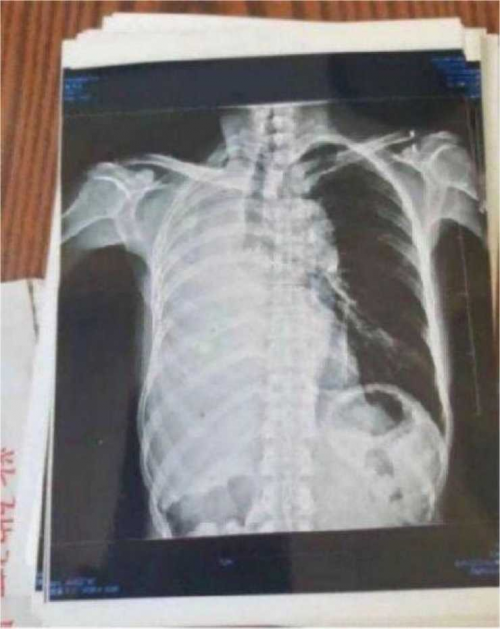

案例5右肺上叶癌(左侧颈部淋巴结转移、鳞状细

胞癌)

患者岂六荣,53岁,系山西省晋中市左权县石匣乡管头村,于2013年1月9日前来就诊。因左胸憋闷,右肺呼吸困难,后背呈放射性疼痛近日加重。于2012年8月7日就诊于山西医科大学第一附属医院,行胸部CT示:右肺上叶癌,行气管镜示;右上叶后段支气管肺癌,右上叶支气管与右中间支气管分膌,右中间支气管开嗳累,病理回报:鳞状细胞癌(病理号12-12929)。于8月30日就诊于山西省肿瘤医院接受治疗。经该院各项检查最后诊断:右上叶癌:左侧颈部淋巴结转移,鳞状细胞癌,化疗后出院于2012年9月19日转山西武警总医院(第一次入院),2012年9月19日。住院期间经过完善的相关检查,期间出现血小板低下,给予升血小板治疗后,血小板恢复正常,后行伽玛刀治疗后,同时给予中药抗肿瘤药今患者及家属要求出院,于2012年10月10日家属要求出院,住院21天。出院诊断;1、右肺上叶癌2、左侧颈部淋巴结转移3、血小板低下,白细胞低下4、乙型肝类(恢复期)。第二次住院(2012年11月9日)出院(2012年11月21日)共住院12天。今患者及家属要求出院,于今日自动出院。

于2o13年1月8日一2o13年5月28日纯中药临床治愈,14o天清零。停药一年半后做医学鉴定:未见肿瘤细胞。至今11年未見复发,未見转移,不服药。一直从事农业劳动。于2024年2月10日(春节)上午10点接通岂六荣电话时,他正赶着羊群往后山上的路上,当我问到中午吃饭怎样解决时:因后山上离村有六七里山路,只有随干粮充饥,并告诉我每天上午10点准时出犮,下午4点半就回到家了。当我问到他身体时:"自从在您那里治好后十一年至今天,不复发,不服药。我很好,很健康,请陈大夫放心”。今天是过大年,你们早点回去,给您拜年,祝您全家新年快乐,平安,幸福!

岂六荣的癌症通过陈老师的高超技艺彻底治愈,前几天陈老师跟他通话他还在山上放羊,山上的温度很低大约在零下二十多度,在山上放羊,追逐羊群,没有好的身体根本不行。现在岂六荣的身体状态特别好,甚至比之前的身体还好。这就是中医药的魅力所在,伟大之处。